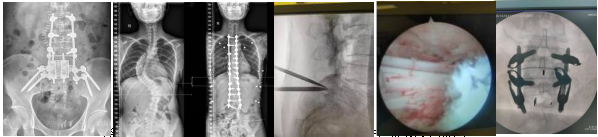

中心下设亚专科—脊柱外科介绍

北京清华长庚医院脊柱外科,作为骨科运动医学中心的核心亚专科,是一支汇聚海内外精英、以高学历高素质医疗人才为骨干、充满活力与创新精神的专业团队。科室依托医院雄厚的综合实力与清华大学顶尖的理工科背景,致力于脊柱疾病的精准诊疗、微创化治疗与快速康复,是医院重点发展的特色专科之一。

脊柱外科开展多项复杂或微创脊柱外科手术诊疗项目

脊柱微创治疗: 科室将微创理念贯穿于诊疗始终,全面常规开展各类国际先进的微创技术,如:内镜技术: 椎间孔镜下腰椎间盘切除术、颈椎Key-hole手术等,切口仅如钥匙孔大小,创伤极小,恢复极快。微创通道技术: MIS-TLIF、OLIF、XLIF等用于治疗腰椎滑脱、椎管狭窄等,避免传统开放手术的大切口与肌肉剥离。经皮穿刺技术: 经皮椎体成形术(PVP)/经皮后凸成形术(PKP)治疗椎体压缩性骨折。微创技术的广泛应用,使众多患者受益于更小的手术创伤、更少的出血、更短的住院时间和更佳的术后恢复效果。

复杂脊柱畸形矫正: 依托强大的多学科协作(MDT)团队,在严重脊柱侧弯、后凸畸形的矫治方面经验丰富,技术达国内先进水平。结合术中导航与神经监测,在追求矫形效果的同时,全力保障神经安全。

颈椎疾病诊疗: 对各类颈椎伤病进行精细化诊断与个体化治疗。从前路ACDF/ACCF、经口咽上颈椎手术、后路Key-hole,到后路椎管扩大成形术、颈椎弓根螺钉内固定、寰枢椎畸形等复杂手术,技术全面,疗效显著。